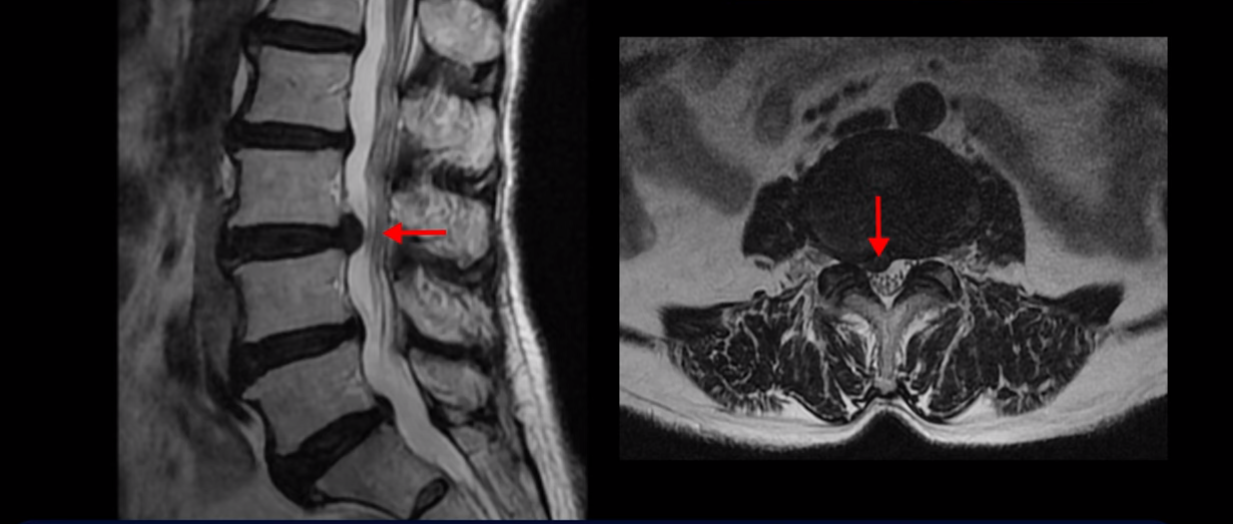

먼저 이분 MRI 보면서 간단히 설명 드린 후 어떻게 신경이 눌려서 수술해야 된다는 환자를 수술 없이 치료할 수 있는지 또 치료는 어떻게 하는지 자세히 설명 드리겠습니다. 이분 허리 MRI를 보면 여러 마디가 퇴행되어 있고

하지만 이 디스크 파열은 오래된 걸로 보이며, 지금 이 환자분의 아픈 양쪽 다리 특히 양쪽 발의 통증, 발 시린 증상과는 관련이 없어 보입니다. 오른쪽 왼쪽의 신경가지가 빠져나가는 추간공을 보면 오른쪽은 5번 1번과 4번 5번이 많이 좁아져 있고

왼쪽은 5번 1번이 많이 좁아져 있습니다.

이렇게 오른쪽 왼쪽 양쪽 추간공들이 다 좁아져 있고 신경가지들이 눌려있으니까 양쪽다리와 양쪽 발이 저리고 시리고 아파서 걷기 어렵습니다. 그런데 이 환자분은 신경주사를 여러 번 맞아도 듣지를 않는데요. 이렇게 신경주사가 듣지 않으면 십중팔구 수술밖에 방법이 없다는 얘기를 듣습니다. 그럼 어떻게 이런 신경이 눌려있는 환자분들을 수술 없이 치료해서 잘 걷게 만들고 다리와 발이 저리고 시리고 아픈 증상이 사라지게 만들까요? 지금부터 설명해드립니다.